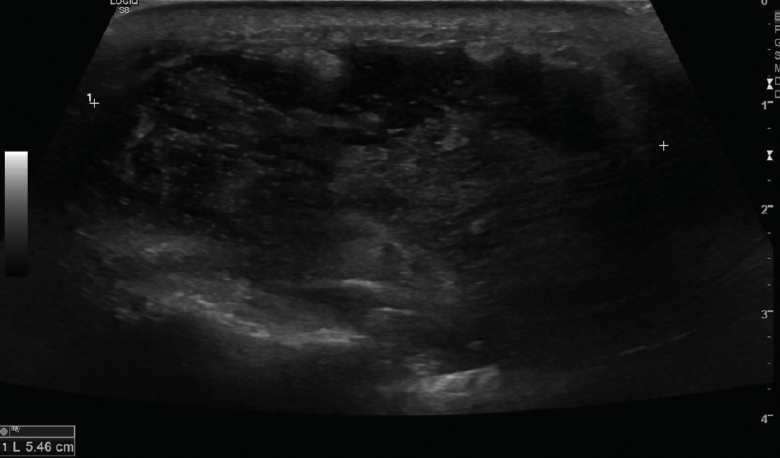

Se observa una colección hipo- o anecoica con refuerzo acústico en lesiones líquidas y sin refuerzo acústico en lesiones sólidas. También puede ser hiperecoica en casos de contenido graso (Figuras 15, 16 y 17).

Figura 16. Corte transversal de una ecografía de pierna: colección hipoecoica intramuscular por hematoma que traduce rotura.

Figura 17. Corte transversal de una ecografía de pierna: colección hipoecoica prepatelar por bursitis muy heterogénea.

4. Bultomas